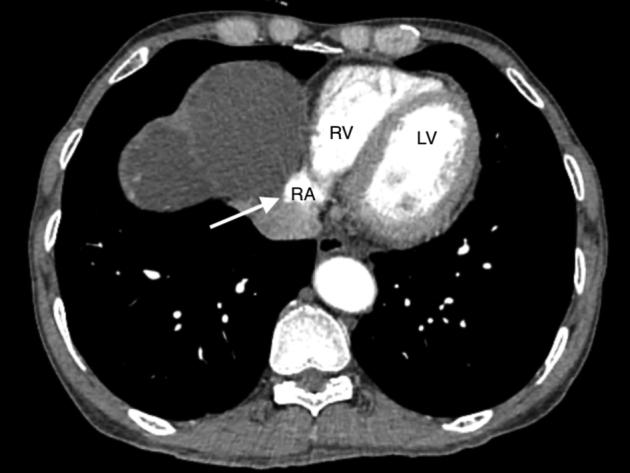

A Case of Hepatic Cyst-Induced Internal Jugular Venous Thrombosis.

• Echocardiography can demonstrate hepatic cyst–induced right atrial compression. • Hepatic cyst–induced blood flow stasis can cause internal jugular venous thrombus. • Laparoscopic deroofing of hepatic cysts is a safe and effective treatment.

• 超声心动图可显示肝囊肿所致的右心房受压。